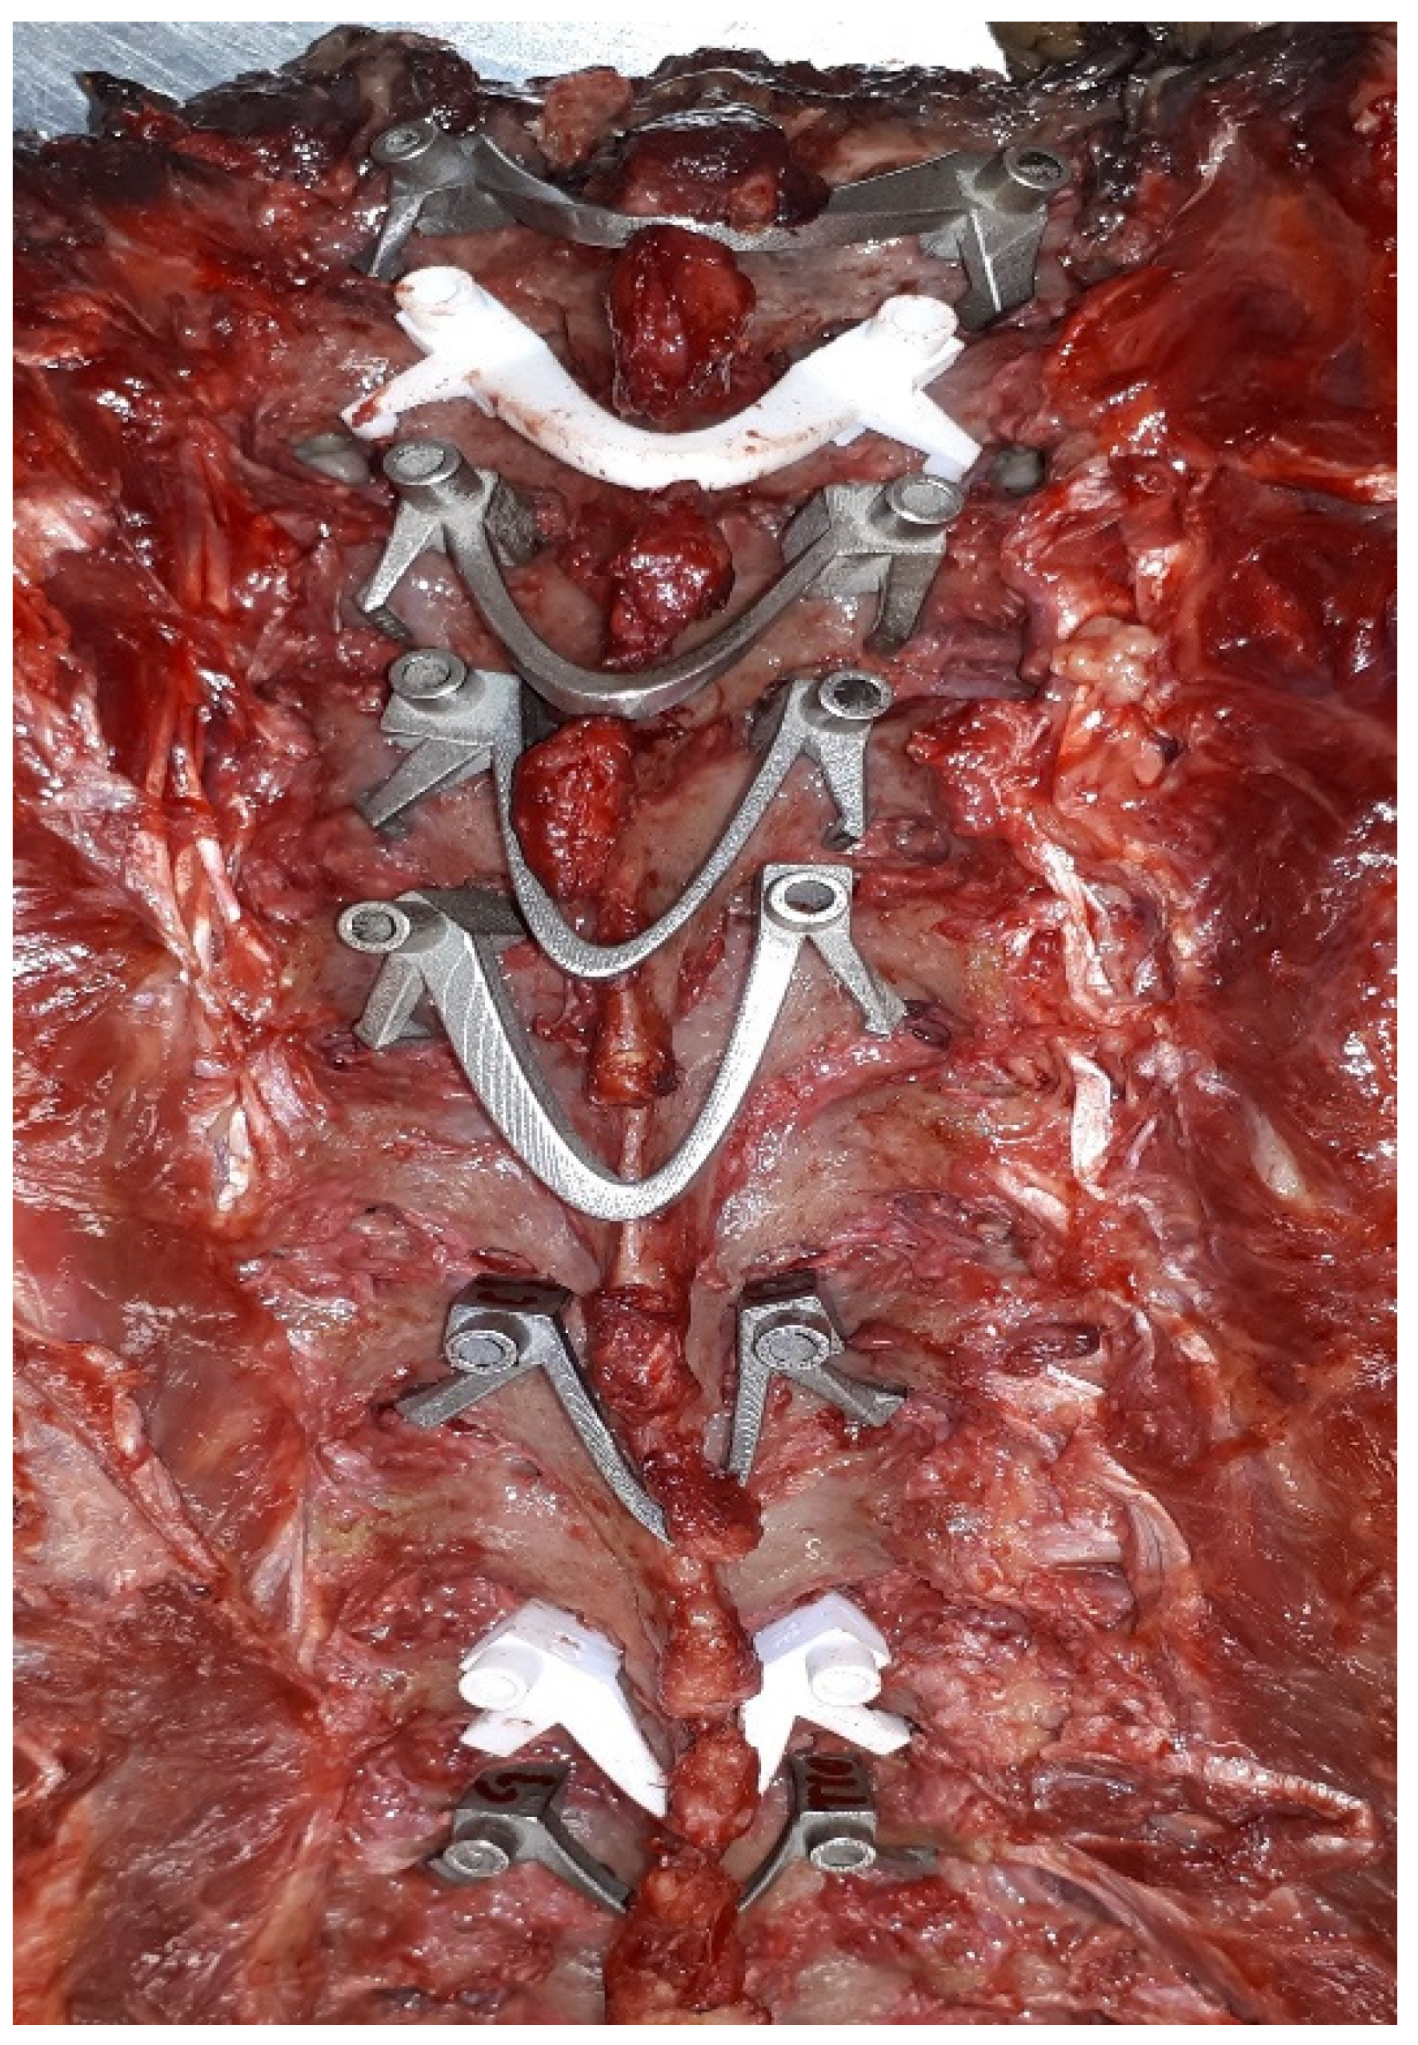

3. Device Description of Click-on Pedicle Guides

3.4. Preclinical Tests

4. Clinical Application